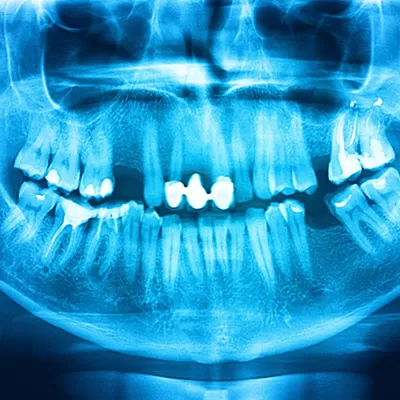

- Narrow or calcified canals that were not initially treated

- Complications of root anatomy

If the treated canal is curved or narrow, it may not have been treated effectively during the initial procedure. Complicated canal anatomy may have been involved that was not detected during the initial procedure. Sometimes, the crown or other restorative device gets delayed after the treatment and results in the root canal failing. The restoration may have been unable to prevent contamination from the saliva.

You should also know that many abscesses begin small and go unnoticed as they don’t cause any pain or discomfort. This is why we suggest that you should maintain your regular dental visits with your dentist. If you had a root canal, it will be monitored during these visits with digital imaging.